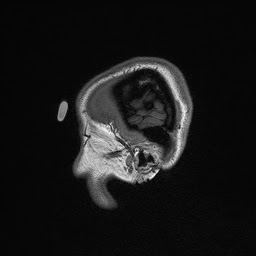

The images are taken in slices beginning from the outside and working its way in—that’s why my brain structures look smaller or bigger in some areas, and why my nose doesn’t show up until the end. And now, without further ado…my brain!

Eventually, when the lab technicians overlaid these images, they were able to create a 3D image of my entire brain, which might have looked something like this: